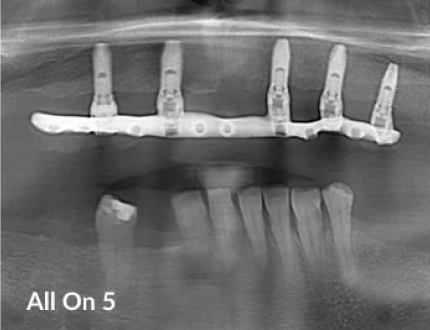

All on 4 is basically a concept of placing a Fixed New Bridge secured onto 4 Dental implants to replace a Full Arch of Teeth. Previous to All on 4 and even today Dentists practice various concepts such as “All on 6” or “All on 5” or “Teeth in a Day” to name a few. At Prosmiles, Melbourne we adapt the All on 4 concepts to the individual needs and make a personalised treatment plan. So, at Prosmiles, your All on 4 Implants are customised to your needs. For example, we may place extra Implants for your Total Teeth Replacement.